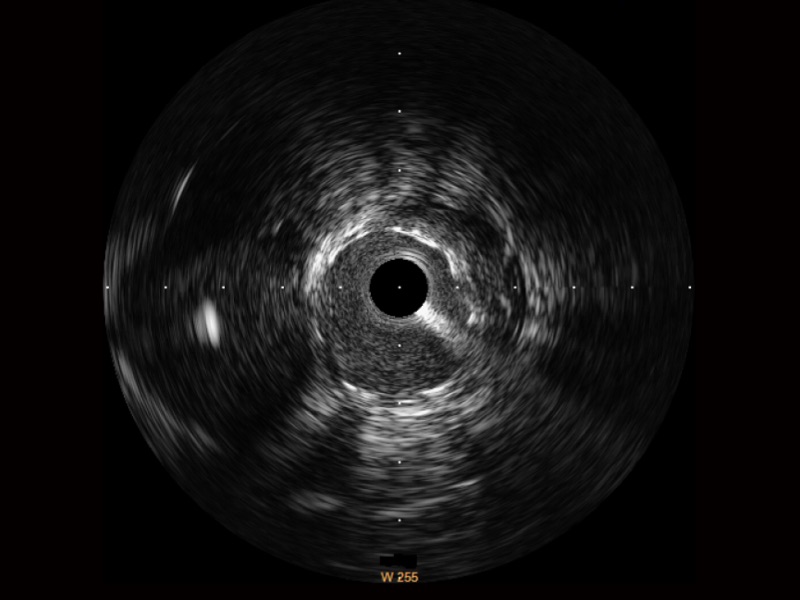

• 传统IVUS图像

对比传统IVUS导管成像,DB中国旗舰官方网站宽频IVUS图像的近场支架梁显影更细腻,远场中膜外血管仍清晰可辨,兼顾远中近,兼顾分辨力与穿透深度